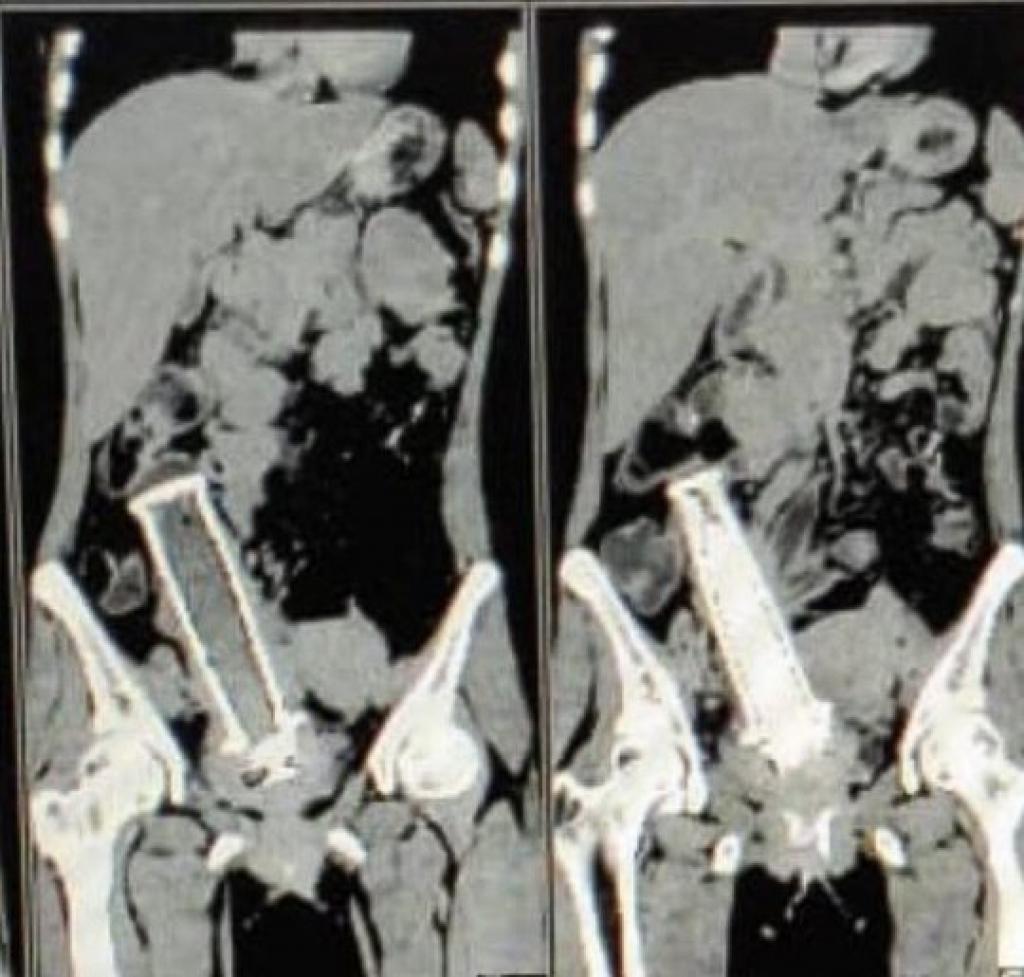

Les docteurs ont donc procédé à une radiographie qui leur a permis de faire une découverte inattendue.

À la grande surprise des médecins, ce qui causait cette douleur était une poignée de moto qui était logée dans l'utérus de la femme et qui s'appuyait sur une partie de son intestin ainsi que sur sa vessie.

Une équipe réunissant 19 docteurs a travaillé pendant 4 heures afin de procéder à l'intervention très délicate.